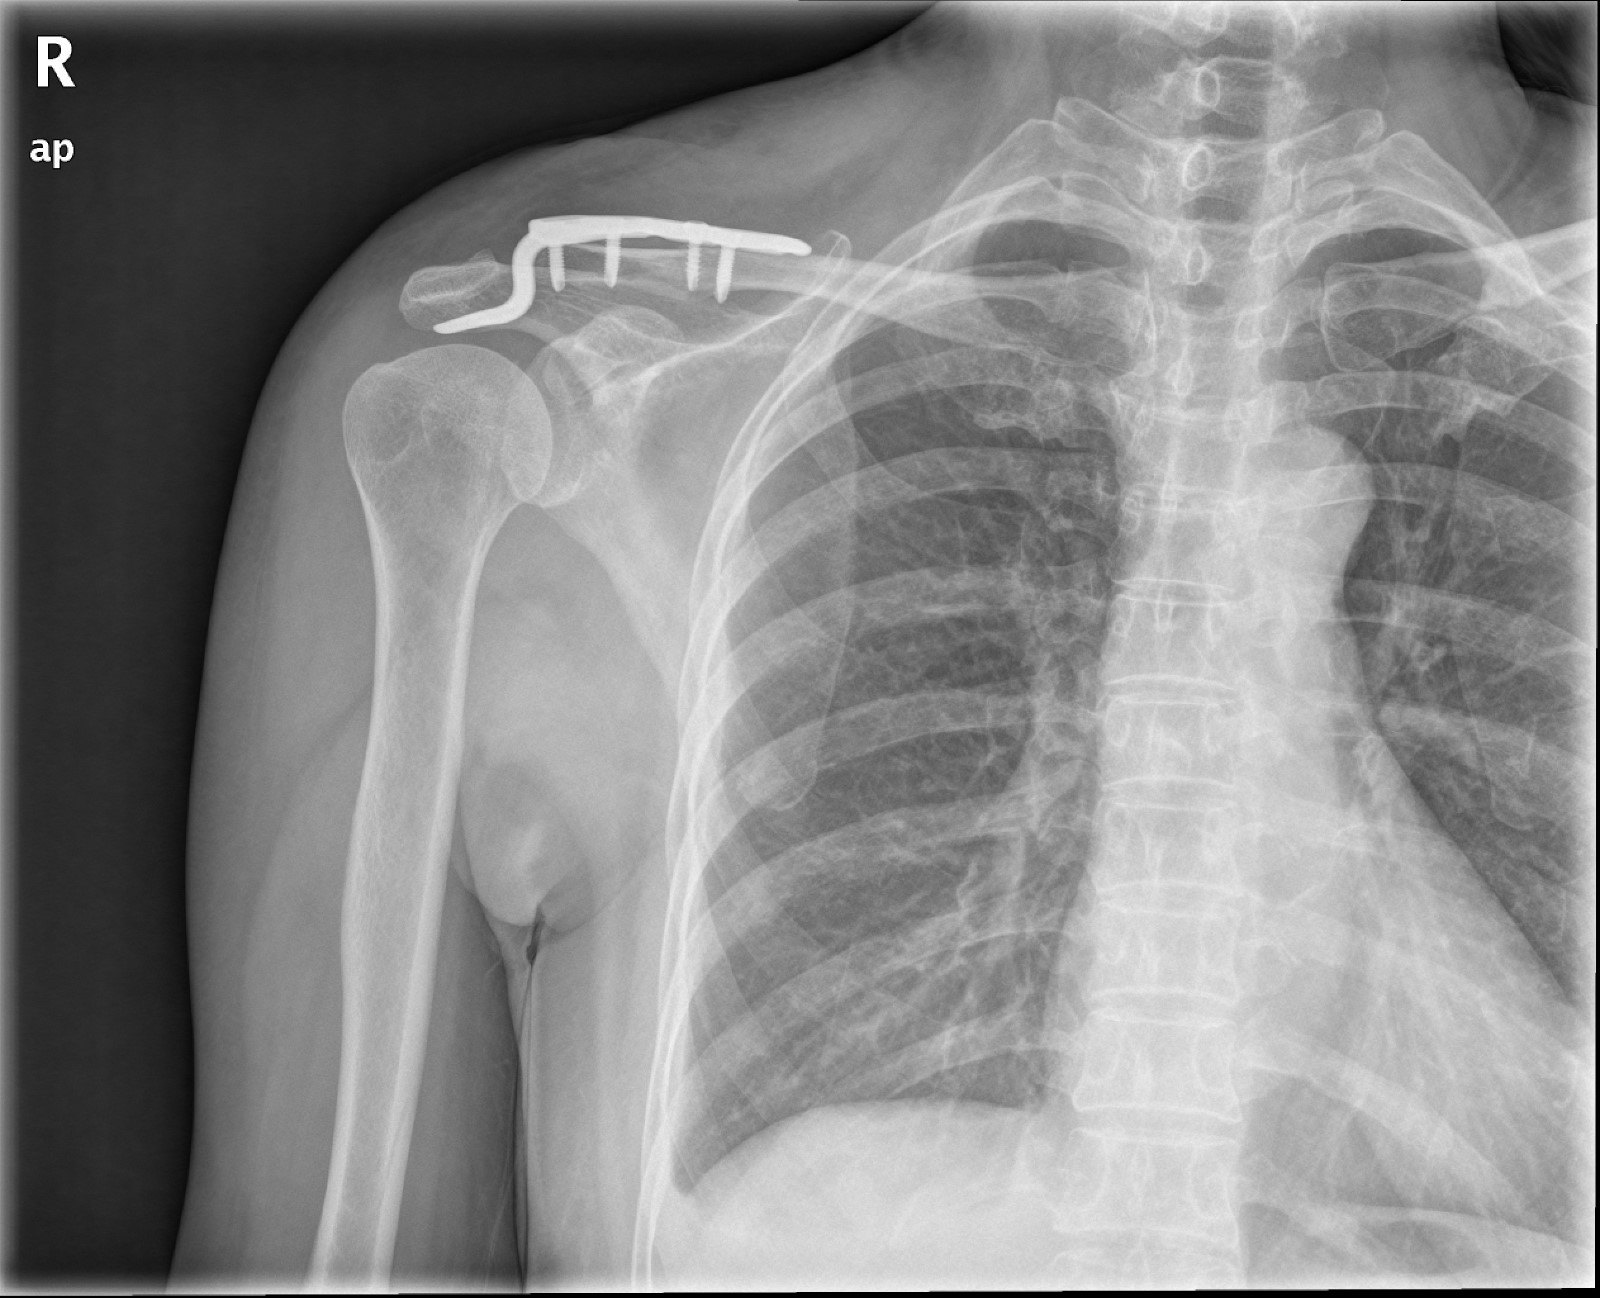

解剖螺旋型互鎖式鋼板鎖骨骨折治療新利器 Ettoday健康雲 Ettoday新聞雲

微創手術治療鎖骨骨折效果佳 Coolanews府城電子報 Pchome 個人新聞台

まあ、今回の鎖骨プレート除去(抜釘)手術は埋め込む時の手術後よりも大分楽でした。 入院期間もプレートを埋め込んだ時は3泊4日で5日間の入院期間を要しましたが、今回は 2日間の入院 で済みました。 入院となると費用の方が気になりますよね。鎖骨骨折をしたら知っておいて欲しいこと 鎖骨バンドは二枚以上必要 鎖骨を骨折して、病院に行くと 鎖骨バンド と呼ばれるものを処方されます。 手術をするほどの怪我の場合はされないことがあります。Mixi鎖骨骨折者 骨が付くまでの期間は 折れかたによって違うのでしょうか? 自分はズレがほとんどないらしいのですが、その方が早く治ったりするのでしょうか? 年齢によっても違うと聞きましたが、みなさんは何歳ぐらいで、どれくらいの怪我でどれくら

・鎖骨のどこを骨折した? ・鎖骨骨折かどうかどうやって分かった? ・治療方法と治療期間は? ・痛みはいつまで続く? ・装具固定中はどんなリハビリをすれば良い? ・骨がくっついたらどんなリハビリをすれば良い? ・骨折どんな服を着れば良い?鎖骨骨折をしたら知っておいて欲しいこと 鎖骨バンドは二枚以上必要 鎖骨を骨折して、病院に行くと 鎖骨バンド と呼ばれるものを処方されます。 手術をするほどの怪我の場合はされないことがあります。鎖骨骨折の治療 鎖骨骨折の治療法は保存療法と手術療法に分けられます。 保存療法 鎖骨骨折は比較的予後が良好であるため、多くは保存療法が選択されます。 骨の転移が大きくなければ整復をして固定する方法が一般的に用いられます。